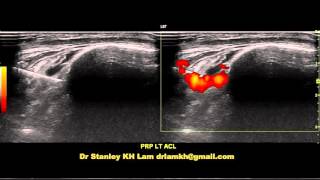

Stanley Lam